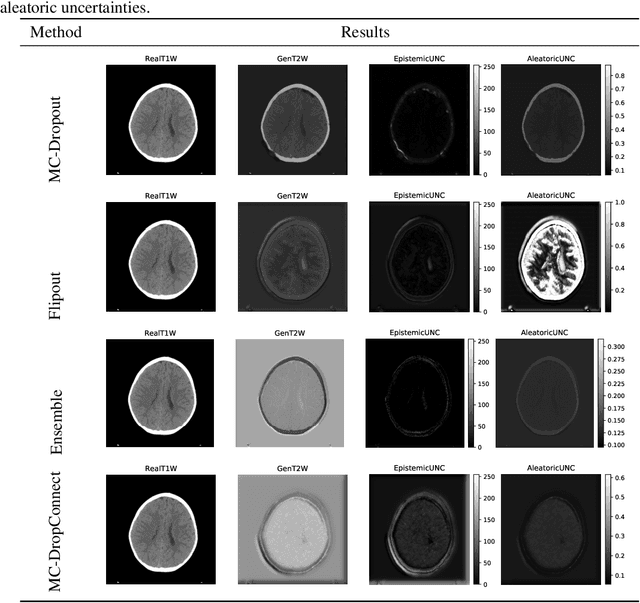

Trusting the predictions of deep learning models in safety critical settings such as the medical domain is still not a viable option. Distentangled uncertainty quantification in the field of medical imaging has received little attention. In this paper, we study disentangled uncertainties in image to image translation tasks in the medical domain. We compare multiple uncertainty quantification methods, namely Ensembles, Flipout, Dropout, and DropConnect, while using CycleGAN to convert T1-weighted brain MRI scans to T2-weighted brain MRI scans. We further evaluate uncertainty behavior in the presence of out of distribution data (Brain CT and RGB Face Images), showing that epistemic uncertainty can be used to detect out of distribution inputs, which should increase reliability of model outputs.